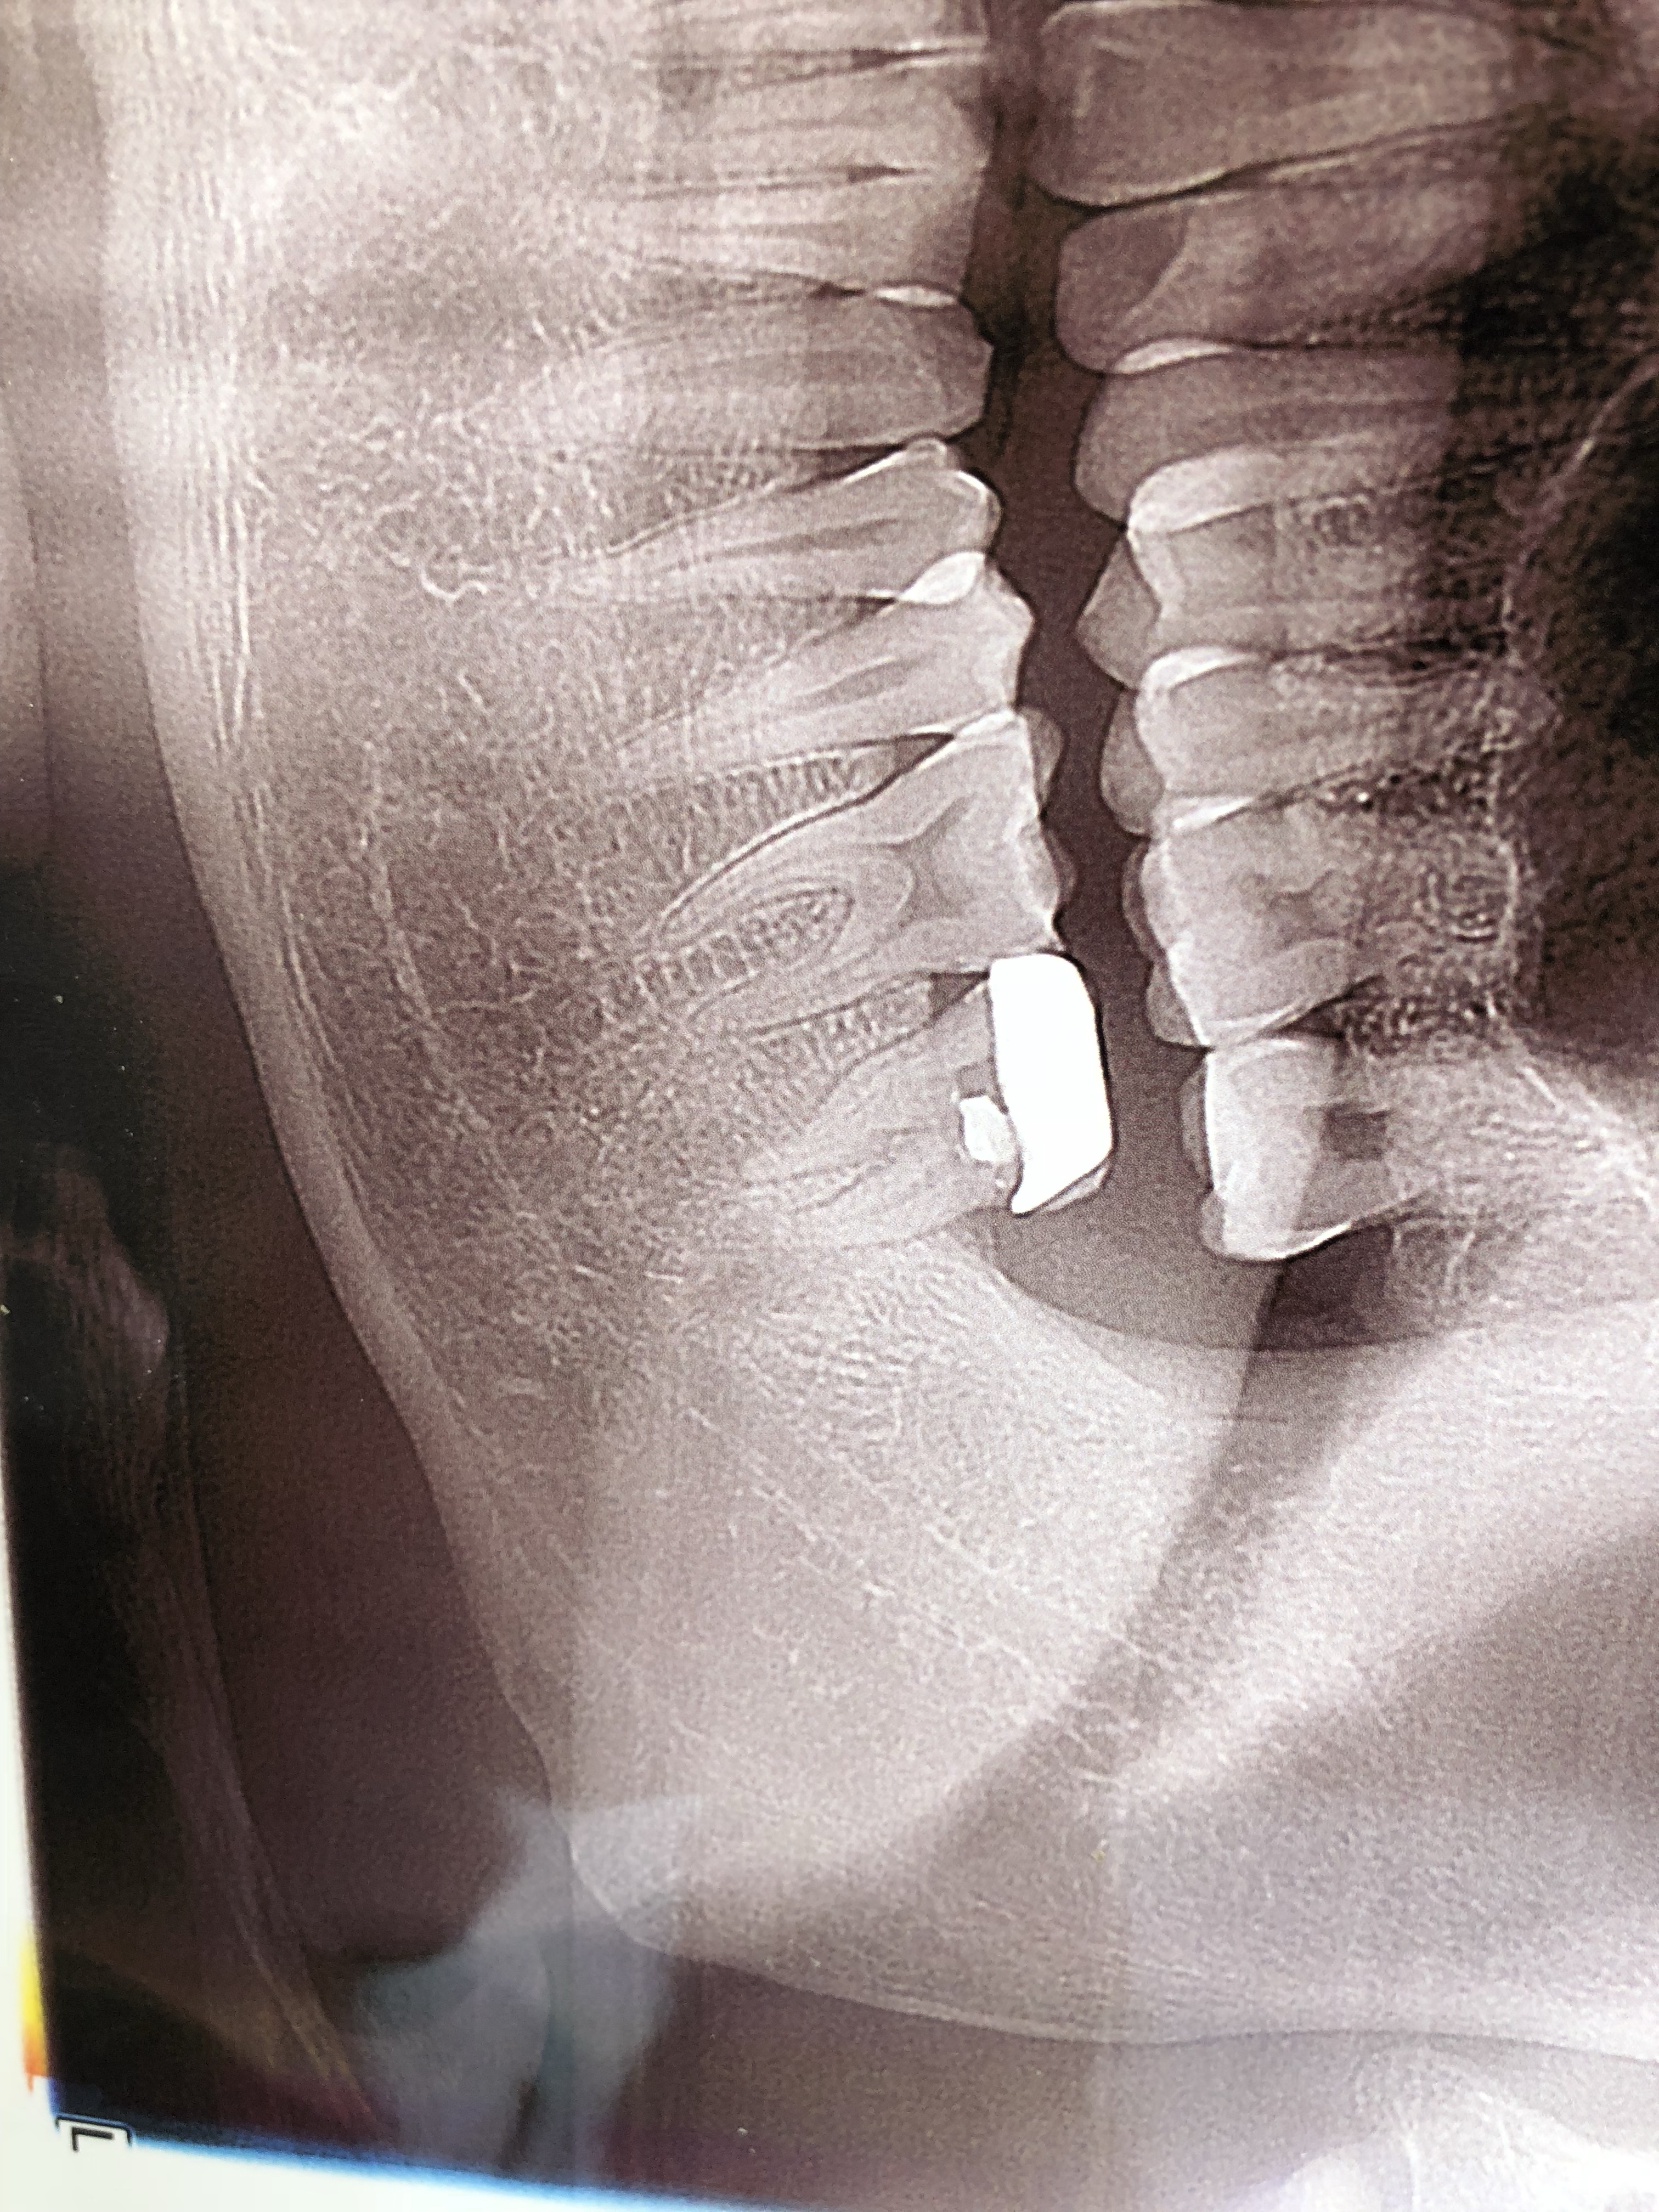

下面最边侧牙齿,牙冠是以前做治疗戴的,现在在牙冠上打孔做的根管,两个牙髓抽掉了一个,另外一个因为上次治疗填充物过硬 医生用工具抽不出牙髓,现在好像没有损坏到牙神经。

PS:医生说我是根尖炎